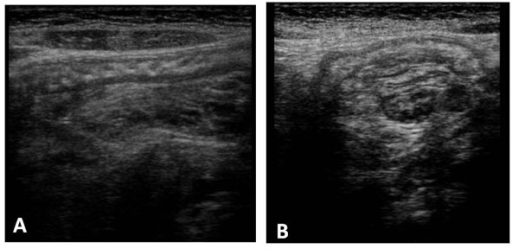

Intussusception in a pediatric patient.